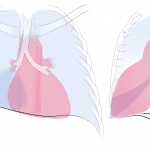

- Blurring of the right heart border on the PA projection with a triangular opacity seen overlying the cardiac silhouette on the lateral projection

- Right middle lobe collapse

- Right middle lobe collapse classically results in a triangular anterior opacity on the lateral view and hazy opacity with loss of the right heart border on frontal view

- Look for evidence of volume loss when trying to decide between atelectasis and consolidation. Signs of volume loss include hemidiaphragm elevation and hilar displacement toward the abnormality